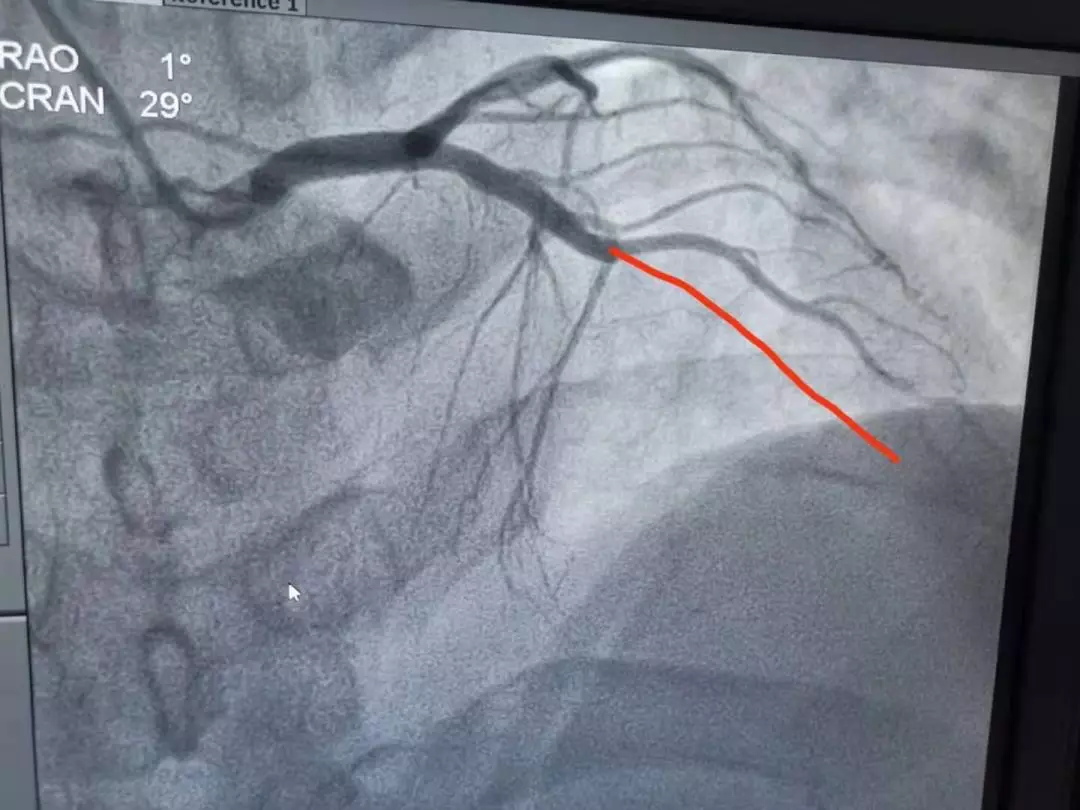

手术室内,李友文主任医师及其团队造影发现,左冠状动脉前降支,中远端100%堵塞,术中出现心肌顿抑,室颤给予电击复律恢复窦性心律,随后给予开通血管的介入治疗。